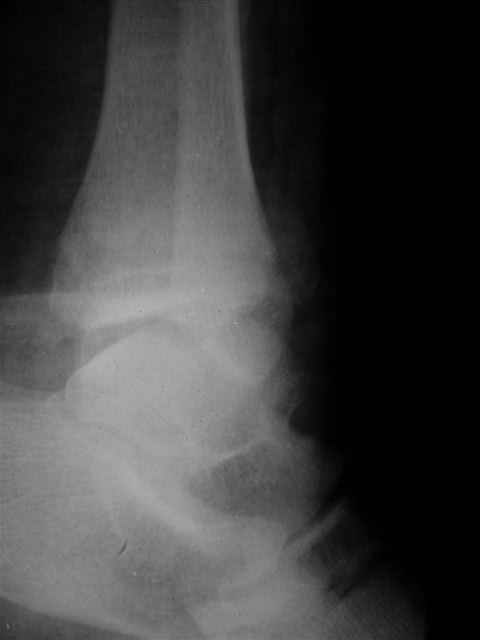

> Если Вас не затруднит, пришлите, пожалуйста, рентгенограммы. Я

> интересуюсь тактикой лечения повреждений голеностопного сустава.

> Хочется посмотреть, как лечат коллеги.

Ничего сверхъестественного, но если есть интерес, то в понедельник пересниму Рг-граммы и отправлю.

Я предупреждал, что ничего сверхъестественного. Каюсь, что одна из спиц прошла несколько дальше, чем нужно было, но главное - перелом стабилизирован и больной работает суставом в полном объёме, несмотря на представленную раннее травму коленного сустава.